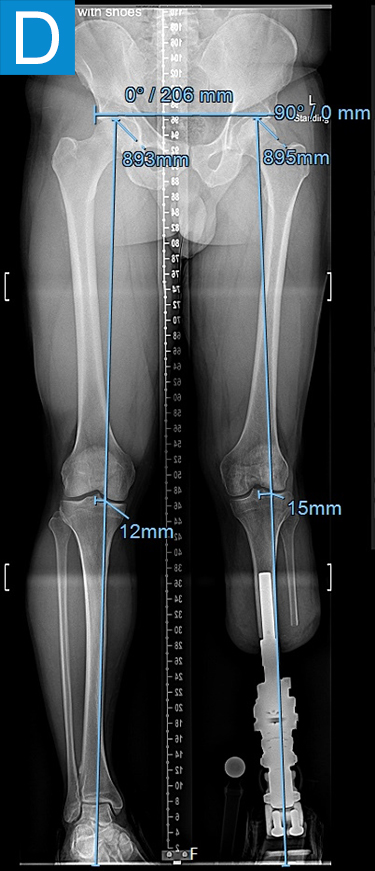

His first surgery was the transtibial amputation with simultaneous osseointegration. This entailed performing amputation of the tibia and fibula at the planned level, reaming and broaching the tibial canal to achieve a uniform canal for the diameter and length of the implant and inserting the osseointegration implant. This feels similar to how a cementless total hip femur implant mixed with an intramedullary nail might feel. Phantom nerve pain was prevented via regenerative peripheral nerve interface technique. Then the skin around the implant that passed through the skin portal was closed. His recovery followed the standard protocol of 4 weeks non-weightbearing followed by 4 weeks of progressive loading, with the prosthesis attached at 2 months (Figure 2). He quickly achieved a better gait than he had prior to amputation (Video 2) with essentially equal swing and stance per leg, but lateral knee pain persisted. Four months after osseointegration, a distal femur osteotomy was performed to neutralize his alignment.

Figure 2. Postoperative clinical photos and radiographs. (A) Front and (B) rear views show the patient standing with the osseointegrated tibia prosthesis. (C) Photo shows stable and healthy skin at portal site to be, although slightly dry due to the winter weather. The gold-colored metal is part of the permanent transcutaneous implant; the shiny silver-colored metal beneath the gold is part of the clinician-removable prosthesis connector, and the matte silver metal beneath features a screw at the front, by which the patient secures the prosthesis. (D) Standing coronal radiograph depicts residual genu valgum in the osseointegrated leg. (E) Lateral radiograph of the osseointegrated tibia. (F) Coronal radiograph of the left knee shows the distal femur osteotomy. (G) Final coronal radiograph after distal femur plate and screw removal shows well-aligned left leg with osseointegrated prosthesis.